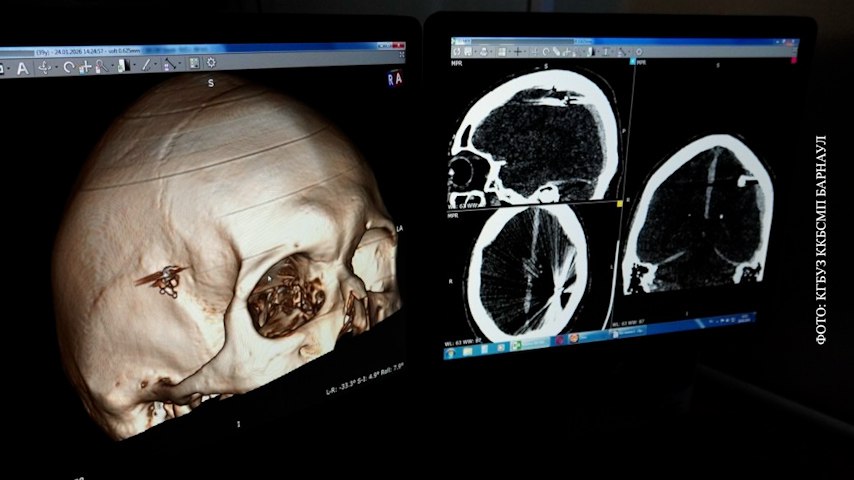

Раненный не пошёл к врачам и попал в больницу, только когда потерял сознание. Оказалось, что в него выстрелили из травмата. Пуля раздробила кости, и осколки попали в мозг. Операция по их извлечению шла 2,5 часа.

Медики убрали всё лишнее из черепа, удалили гематому и спасли пациента. Сможет ли он жить полноценно — пока неизвестно. Пока впереди долгая реабилитация.